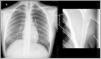

Synovial sarcoma (SS) is a rare malignant neoplasm of the soft tissue adjacent to joints. It is the most commonly diagnosed non-rhabdomyosarcoma soft-tissue sarcoma (STS) in childhood (30%). Its most frequent location is the knee and ankle, and it is the most common STS to affect the foot. Unlike other STS, it has slow growth and an earlier age at diagnosis (adolescents and young adults), which is why many cases are initially misdiagnosed as benign processes. Magnetic resonance imaging (MRI) is key due to its characterisation capabilities as SS shares features with other STS. Definitive diagnosis is achieved through a pathological study that shows the pathognomonic translocation t(x;18)(p11;q11) with the fluorescence in situ hybridisation (FISH) technique. The objective of this article is to highlight the key characteristics that are useful for diagnosing SS, fundamentally through the use of radiological imaging techniques, as well as nuclear medicine and pathological studies, illustrated with cases diagnosed in our centre.

El sarcoma sinovial (SS) es una neoplasia maligna infrecuente del tejido blando adyacente a las articulaciones, siendo el sarcoma de tejidos blandos (STB) de tipo «no rabdomiosarcoma», más diagnosticado en la infancia (30%). Su localización más frecuente es la rodilla y tobillo, representando el STB más común del pie. A diferencia de otros STB, presenta un crecimiento lento y una edad más temprana al diagnóstico (adolescentes y adultos jóvenes), por lo que muchos casos son inicialmente diagnosticados como procesos benignos de forma errónea. La resonancia magnética (RM) es clave para su caracterización, si bien comparte características con otros STB. El diagnóstico definitivo es anatomopatológico, que evidencia la translocación patognomónica t(x;18)(p11;q11) con técnica de hibridación fluorescente in situ (FISH). El objetivo de este artículo, ilustrado con casos diagnosticados en nuestro centro, es resaltar las características claves para el enfoque diagnóstico del SS, fundamentalmente mediante el uso de técnicas de imagen radiológicas, así como estudios de medicina nuclear y anatomopatológicos.